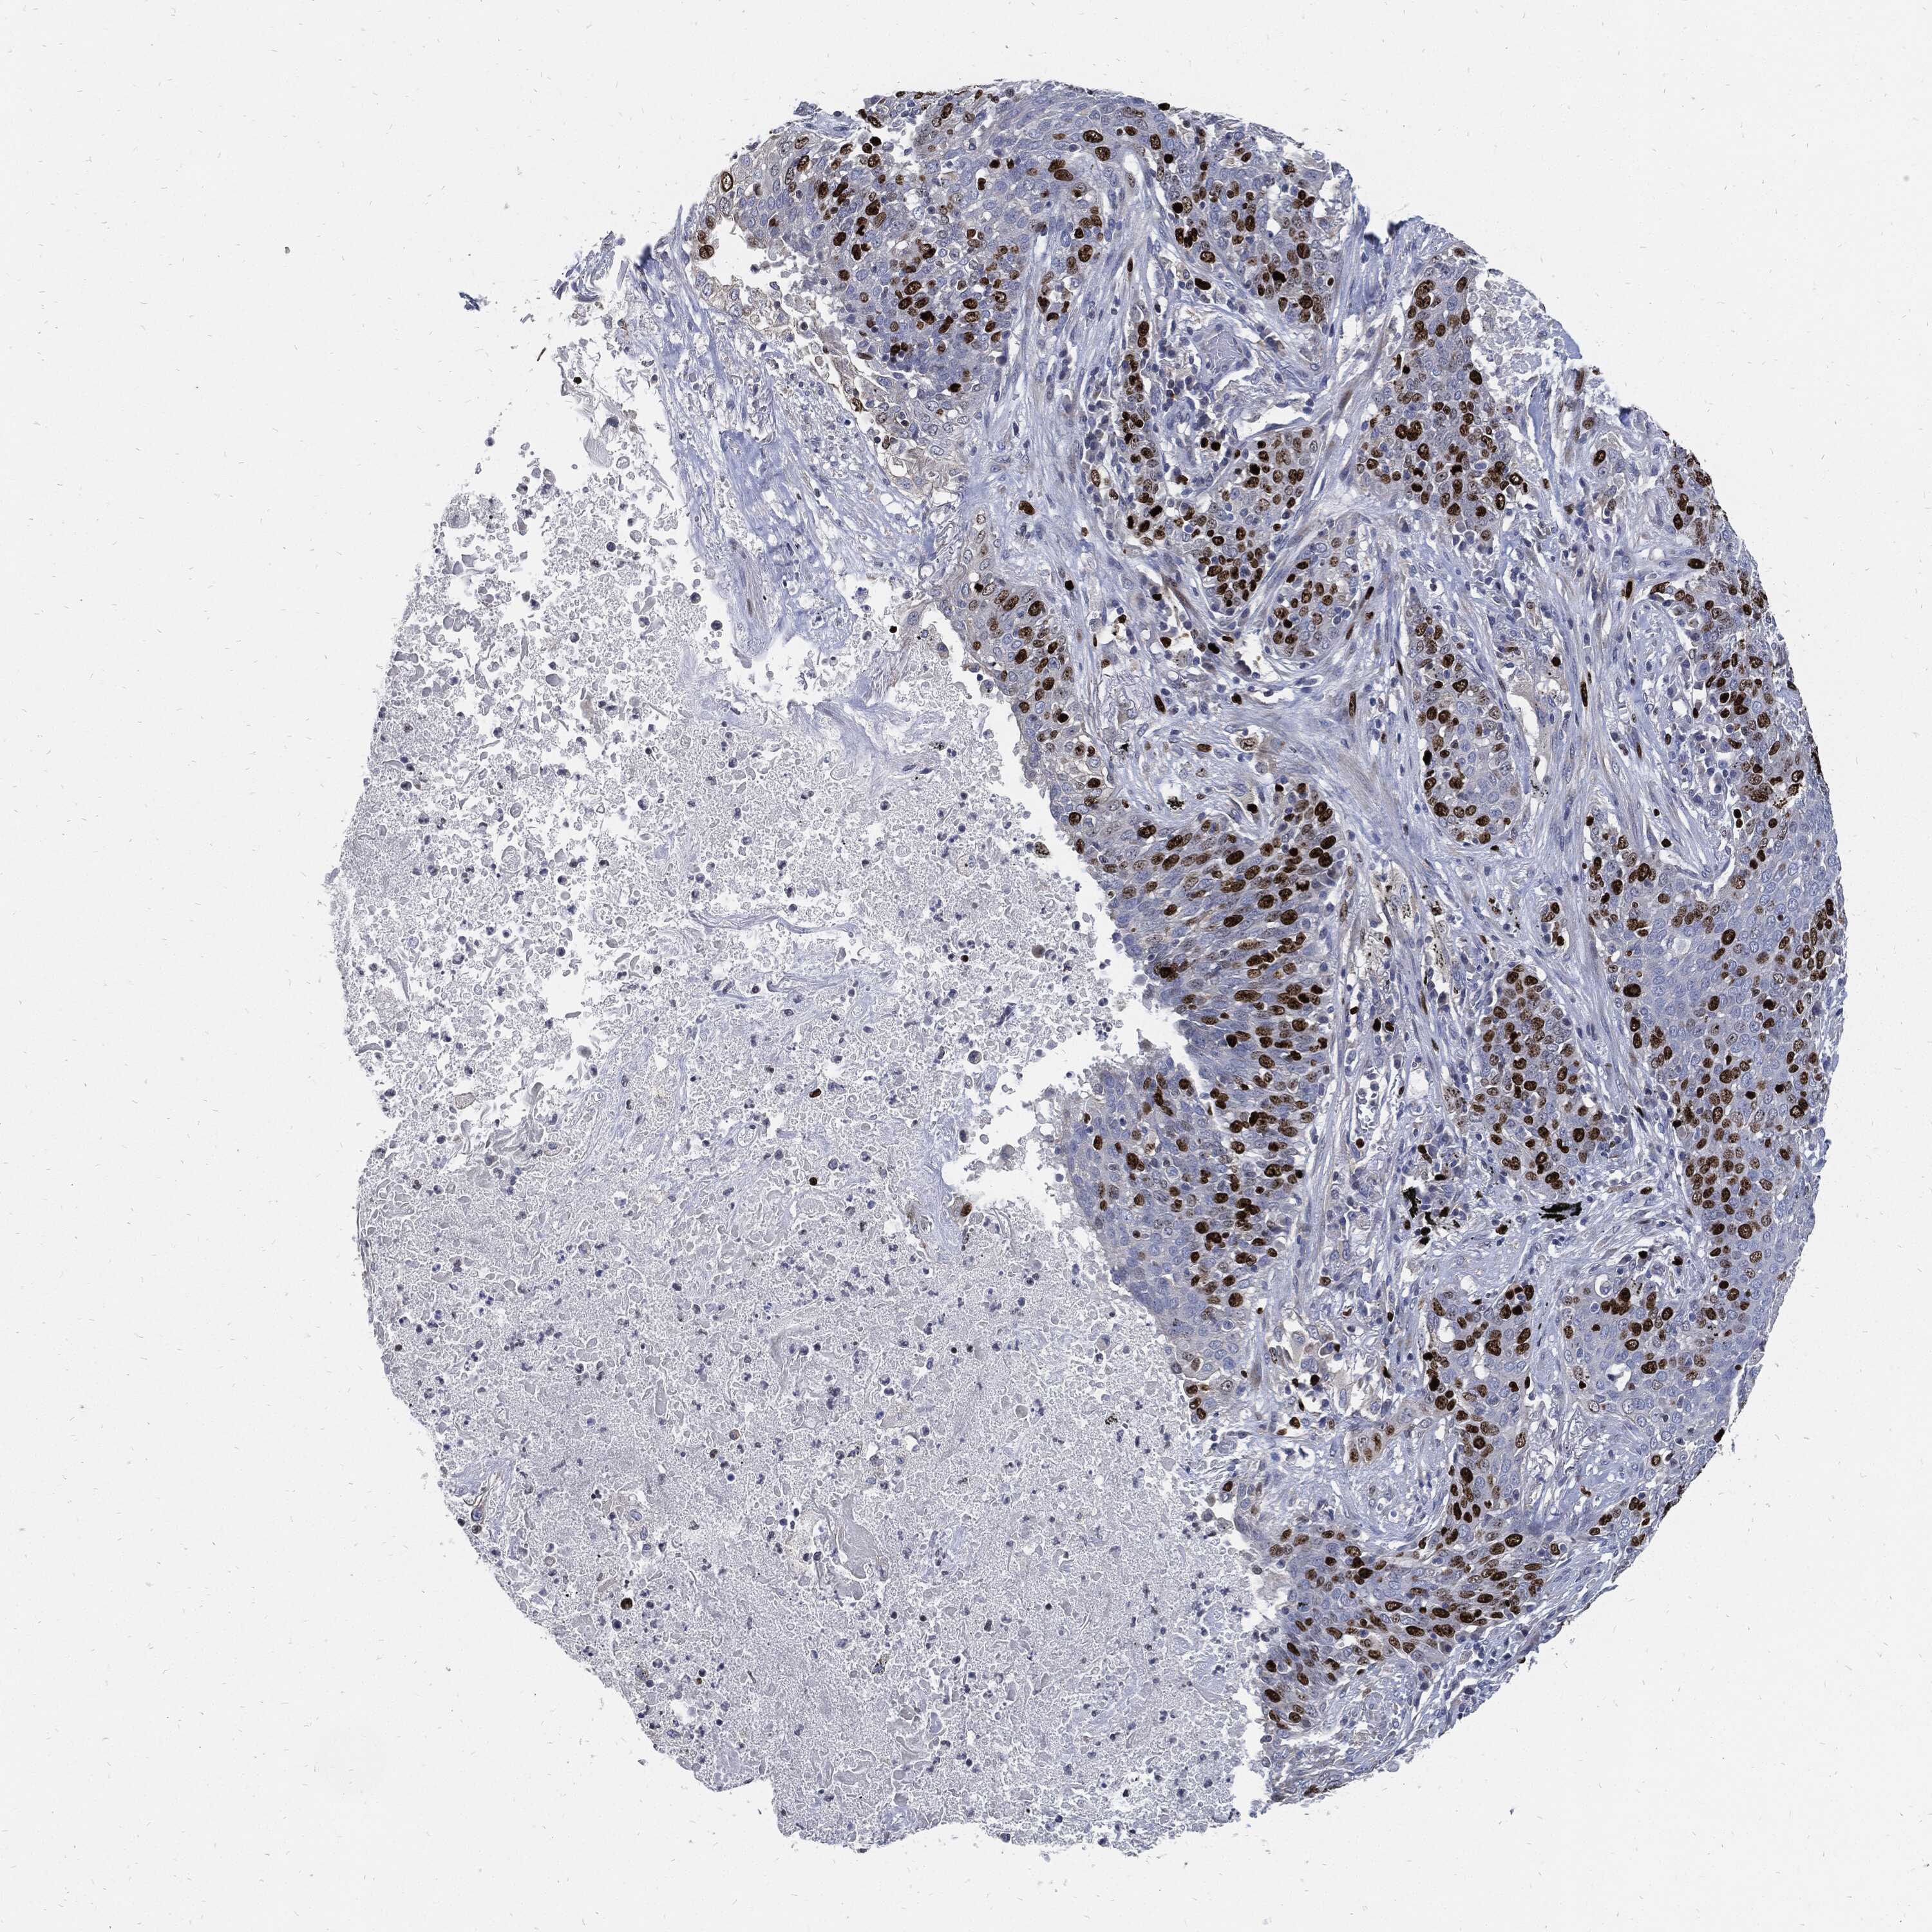

MKI67 is validated prognostic, high expression is unfavorable in Lung Adenocarcinoma (validation)

: 8.83

Average pTPM 9.2

Number of samples 105